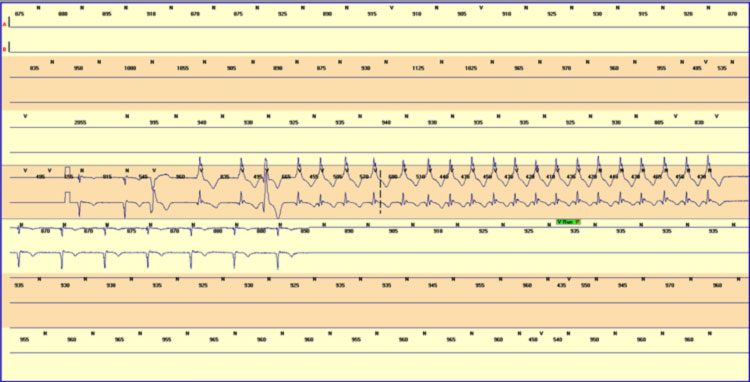

ECG basale e ECG dinamico secondo Holter: I marker elettrocardiografici di rischio aritmico possono essere la presenza di QRS frammentato e la presenza di micro-alternanza dell’onda T, anche se tali parametri non sono stati ancora valutati in maniera prospettica. Altri marker ECG sono il riconoscimento di aritmie sopraventricolari o ventricolari, in particolare tachicardie ventricolari non sostenute durante registrazione Holter, in particolare Holter prolungato.